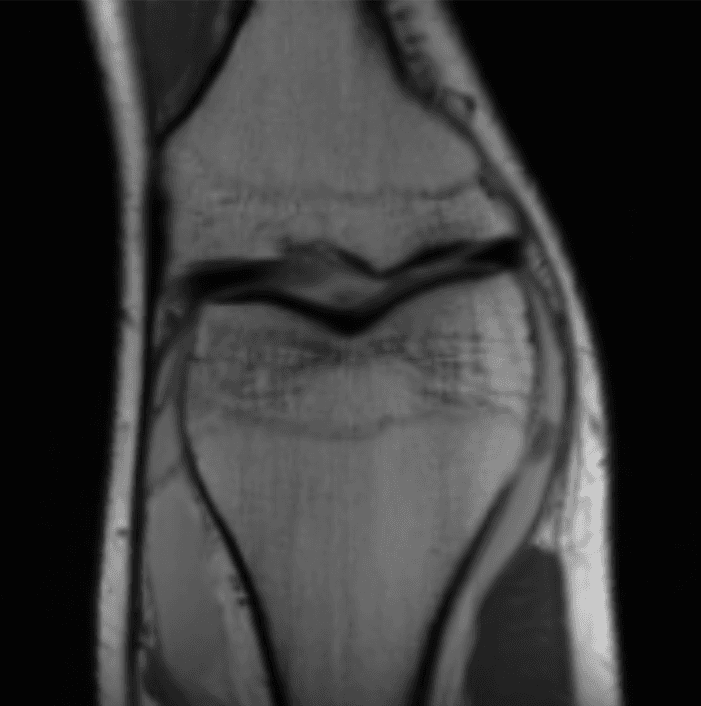

[Tell me a funny story about this study]Below is a sample reconstruction from their study, compared with the ground truth. I can't tell the difference.

Knee MRI comparison between VarNet and the ground truth at 4x acceleration. Figure reproduced from Recht et al. 2020.